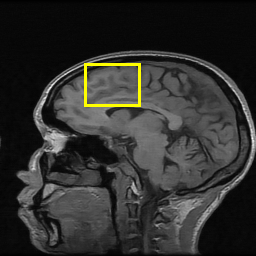

Edge preserving has always been a crucial concern in the design of reconstruction models. To improve the quality of reconstructed images and preserve image edges, some works suggested introducing edge priors in the original restoration problem to preserve image edges [4, 34]. However, they will suffer from complicated algorithm design and time-consuming training processes. Recently, some more efficient methods have been proposed to use edge maps as external guidance for image restoration. For example, Yang et al. [48] used off-the-shelf edge detectors to extract image edges from the degraded images. Fang et al. [12] predicted image edges by constructing an edge reconstruction network. Huang et al. [18] designed a novel dual discriminator GAN framework for solving fast multi-channel MRI, in which one GAN network is built for edge information enhancement. Inspired by these methods, we also consider introducing image edge prior as external guidance to MRI reconstruction since 1) image edges are prominent and distinguishable features in MRI (see Fig. 1), which can serve as a good guide to the model to recover high-frequency details; 2) the ground truth edges can be easily fetched via ordinary edge extraction operators, like Canny, Sobel, and Prewitt, which means that the edge maps can be learned in a data-driven manner. However, how to effectively utilize image edge priors to guide image reconstruction still remains a challenge. In some methods, edge information was simply concatenated with the input image and passed to the next stages. Though this is a simple way to utilize the edge priors, it may not give full play to the guiding role of the edge priors. Therefore, in this work, we want to explore a more efficient and effective mechanism to fully take advantage of image edge priors.

(a)

(b)

(c)

fastMRI is a large-scale MR dataset jointly established by Facebook AI Research and NYU Langone Health. It provides both knee and brain datasets for evaluation. In our work, we use the multi-coil knee dataset, which was acquired on three clinical 3T systems or one clinical 1.5T system using a 15-channel knee coil array. The dataset includes data from two pulse sequences, yielding coronal proton-density weighting with (PDFS) and without (PD) fat suppression. As is shown in Fig. 1, PD images usually contain more structural and prominent edge features than PDFS images, which suggests that it is more challenging to use edge guidance on PDFS datasets. Therefore, we explore the effectiveness of EAMRI on these two modalities. Following [13], for both PD and PDFS knee datasets, we separately filter out 227 volumes (8332 slices) for training and 24 volumes (1665 slices) for testing. The dataset is centrally cropped to .

EPN is utilized to provide edge priors for later reconstruction, so the quality of the predicted edges is very important. In Fig. 10, we provide some qualitative results of the predicted edges of EPN on three multi-coil datasets. Among them, the GT edges are extracted using the Sobel operator. As can be seen from the images, our proposed EPN can predict an approximate contour for the overall subject and can reconstruct accurate edges close to the GT edges under two acceleration factors. This fully verifies the effectiveness and excellence of the proposed EPN.